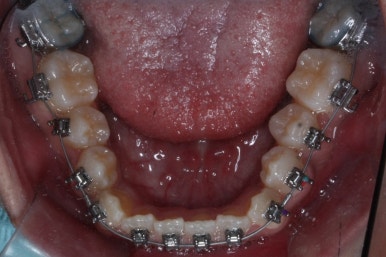

위 사진들은 부산주걱턱교정 키다리아저씨치과에 내원하셨을 당시의 입안 모습입니다.

입 안의 모습에서도 주걱턱의 특징으로는

하악이 앞으로 나와있습니다.

윗니는 뻐드러지고 아래 앞니는 뒤쪽으로 쓰러져 있습니다.

교합이 맞지 않습니다.